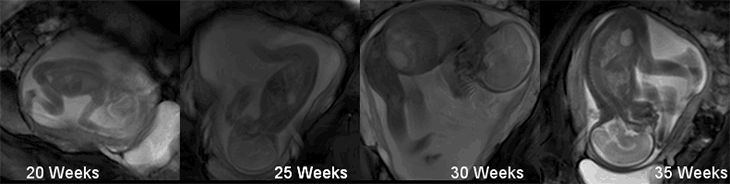

Along with bioengineer Niamh Nowlan, of ICL, and colleagues, Verbruggen analyzed videos of fetal kicks caught on MRI scans. These scans, from multiple pregnant women, included clear leg kicks at 20, 25, 30 and 35 weeks gestation. Other MRI scans provided anatomical details about bones, joints and leg sizes. With sophisticated math and computational models, the researchers could estimate the strengths of the kicks, as well as the mechanical effects, such as stresses and strains, that those kicks put on fetal bones and joints.

Kicks ramped up and became more forceful from 20 to 30 weeks, the researchers found. During this time, kicks shifted the wall of the uterus by about 11 millimeters on average, the team found. But by 35 weeks, kick force had declined, and the uterus moved less with each kick, only about 4 millimeters on average. (By this stage, things are getting pretty tight and tissues might be stretched taut, so this decrease makes sense.) Yet even with this apparent drop in force, the stresses experienced by the fetus during kicks kept increasing, even until 35 weeks. Increasing pressure on the leg bones and joints probably help the fetus grow, the researchers write.